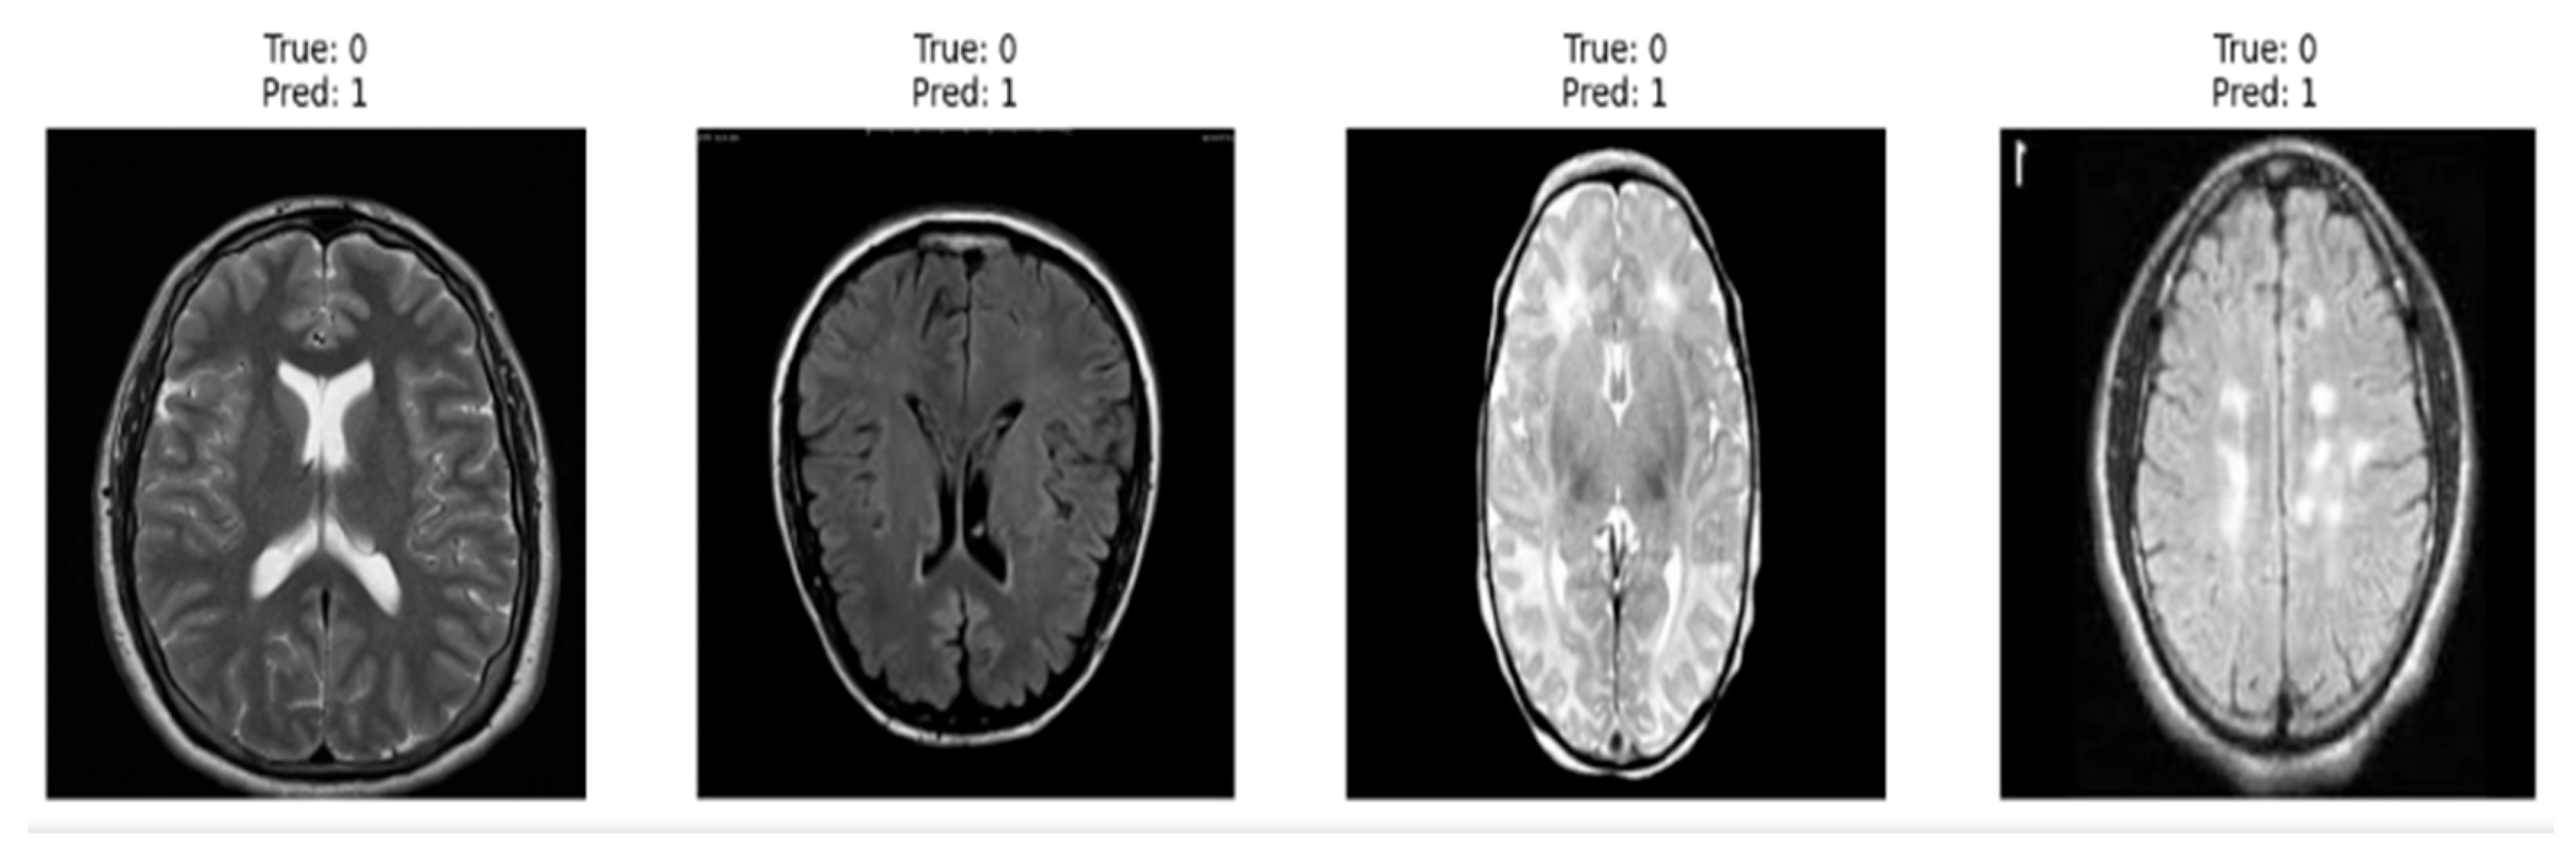

The EfficientNetB4 model demonstrated outstanding performance, achieving an F1-score of 100% on the test set. Out of 300 test images, only one instance was misclassified, indicating exceptionally high precision and recall. Figure 12 presents a sample prediction output of the model, further illustrating its strong capability in distinguishing between tumor and non-tumor MRI images.

This section presents a comparative analysis of the deep learning models evaluated in this study, namely CNN, VGG16, and EfficientNetB4. As shown in the Classification Report Heatmap in Figure 13, the EfficientNetB4 model achieved perfect performance, obtaining precision, recall, and F1-score values of 1.00 for both tumor (YES) and non-tumor (NO) categories using 999 test samples. These results indicate that the model correctly classified all instances without any misclassifications, demonstrating 100% classification accuracy.

The superior performance of EfficientNetB4 highlights the effectiveness of its compound scaling strategy and advanced feature extraction capabilities, proving its advantage over traditional CNN and VGG16 architectures in MRI-based brain tumor detection. The Confusion Matrix presented in Figure 14 provides a visual representation of the model’s classification performance. Out of 400 test samples, only two instances were misclassified—one as a false positive and one as a false negative—resulting in an impressive overall accuracy of 99.5%. The strong diagonal dominance within the matrix highlights the model’s high discriminative capability and its ability to accurately distinguish between tumor and non-tumor MRI scans.